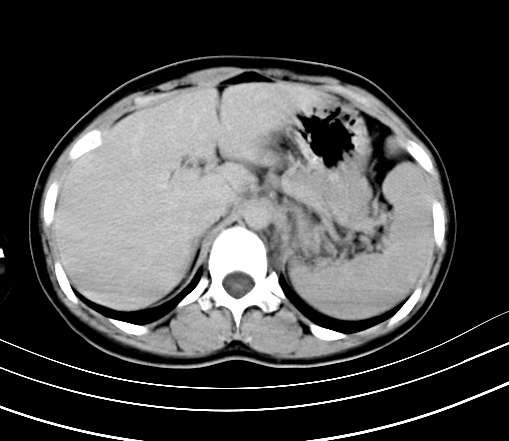

静脉期